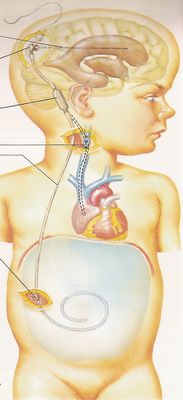

Вентрикуло-перитонеальный шунт: Показания и применение

Раздел: Фотоальбом решений